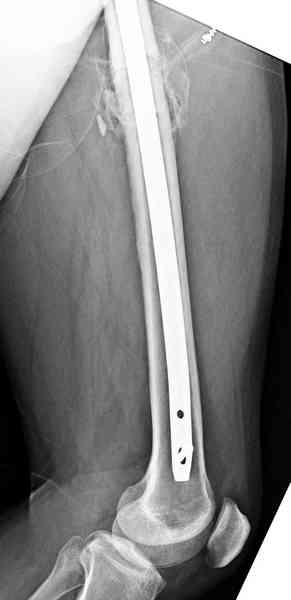

Здесь представлены снимки больного 65 лет, поступившего с диагнозом перелом

бедра после автоаварии.

В первый же день произведено антеградное штифтованием DePuy Trochanteric Nail.

На второй день (7) обнаружен пропущенный перелом,

сделаны Компьютерная Томограмма

и проведены шурурпы через и спереди штифта без удаления.

Послеоперационные снимки